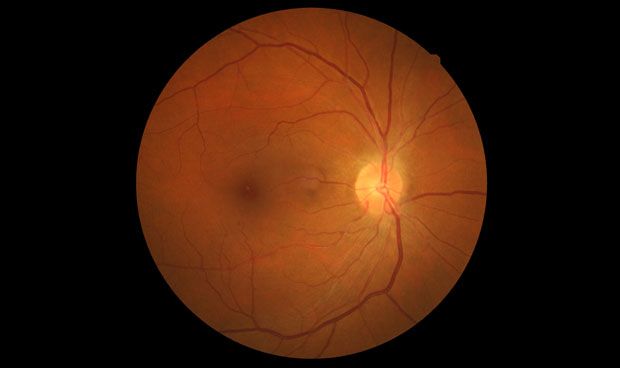

Las personas con enfermedad renal crónica presentan un riesgo mucho mayor de enfermedad cardiovascular, la principal causa de muerte para las personas con diabetes tipo 1. En un artículo publicado en Diabetes Care, el equipo de Joslin demostró que la afección ocular conocida como retinopatía diabética proliferativa también se vincula de forma independiente con la enfermedad cardiovascular.

El daño a los nervios entre los pacientes con diabetes tipo 1 no muestra los mismos vínculos con las enfermedades cardiovasculares que el daño ocular, lo que sugiere una estrecha conexión entre el daño en el ojo y el cardiovascular. Entre los próximos pasos, los científicos analizarán imágenes del corazón de varios grupos de Medalist para buscar vínculos más detallados entre el daño en los músculos del corazón y el daño a otros órganos. "Esperamos que nos brinde el siguiente conjunto de pistas para comprender y proteger contra estas complicaciones", concluye King.